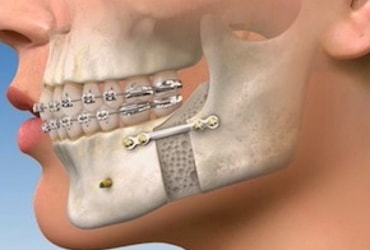

TMJ Surgeries

The point where the jawbone and the skull meet that joint is known as the temporomandibular...

Orthodontic Treatment

The procedure to improve the look and appearance of the oral cavity and to straighten the...

Braces

Braces can straighten teeth, line up your jaws to give you a better bite, space out crowded...